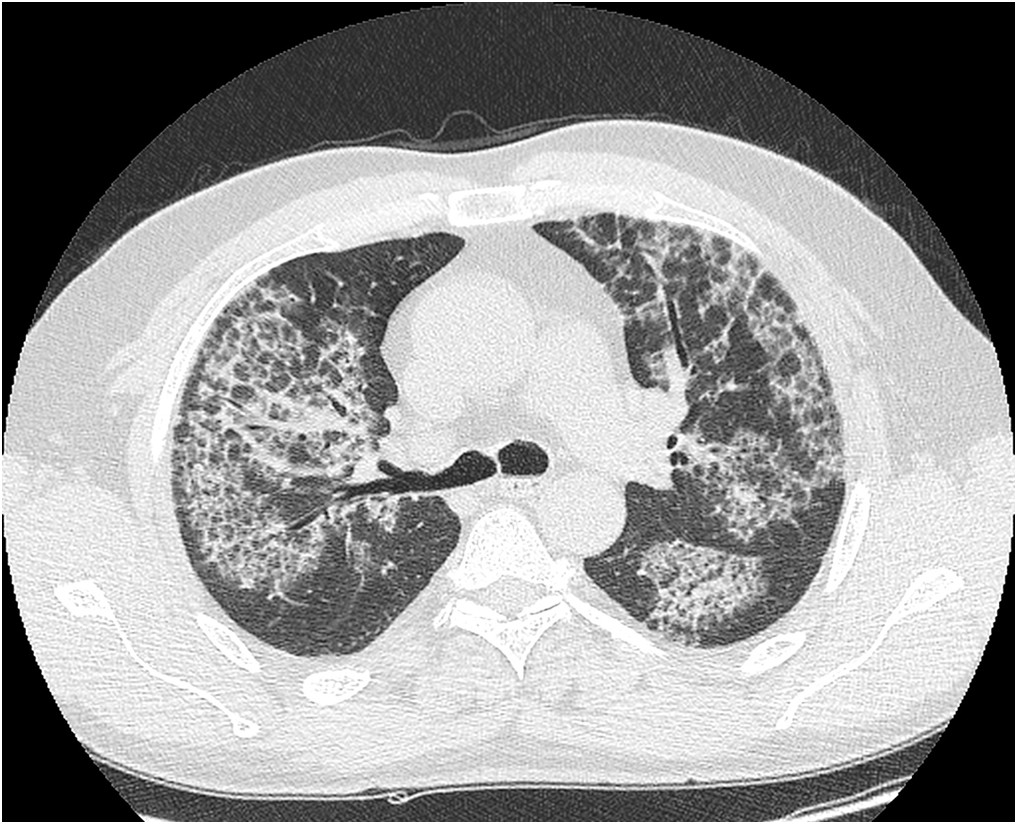

Pacjent l. 40 zgłosił się do lekarza rodzinnego z powodu suchego męczącego kaszlu, mniejszej tolerancji wysiłku, szybszego męczenia się od około 3 miesięcy. Bez cech infekcji. Dotychczas nie chorował. Nie palił i nie pali. Po wykonaniu zdjęcia radiologicznego klatki piersiowej na którym stwierdzono zmiany skierowano pacjenta na KT klatki piersiowej na którym uwidoczniono niżej pokazane zmiany.

Obraz KT najbardziej przypomina obraz spotykany w: